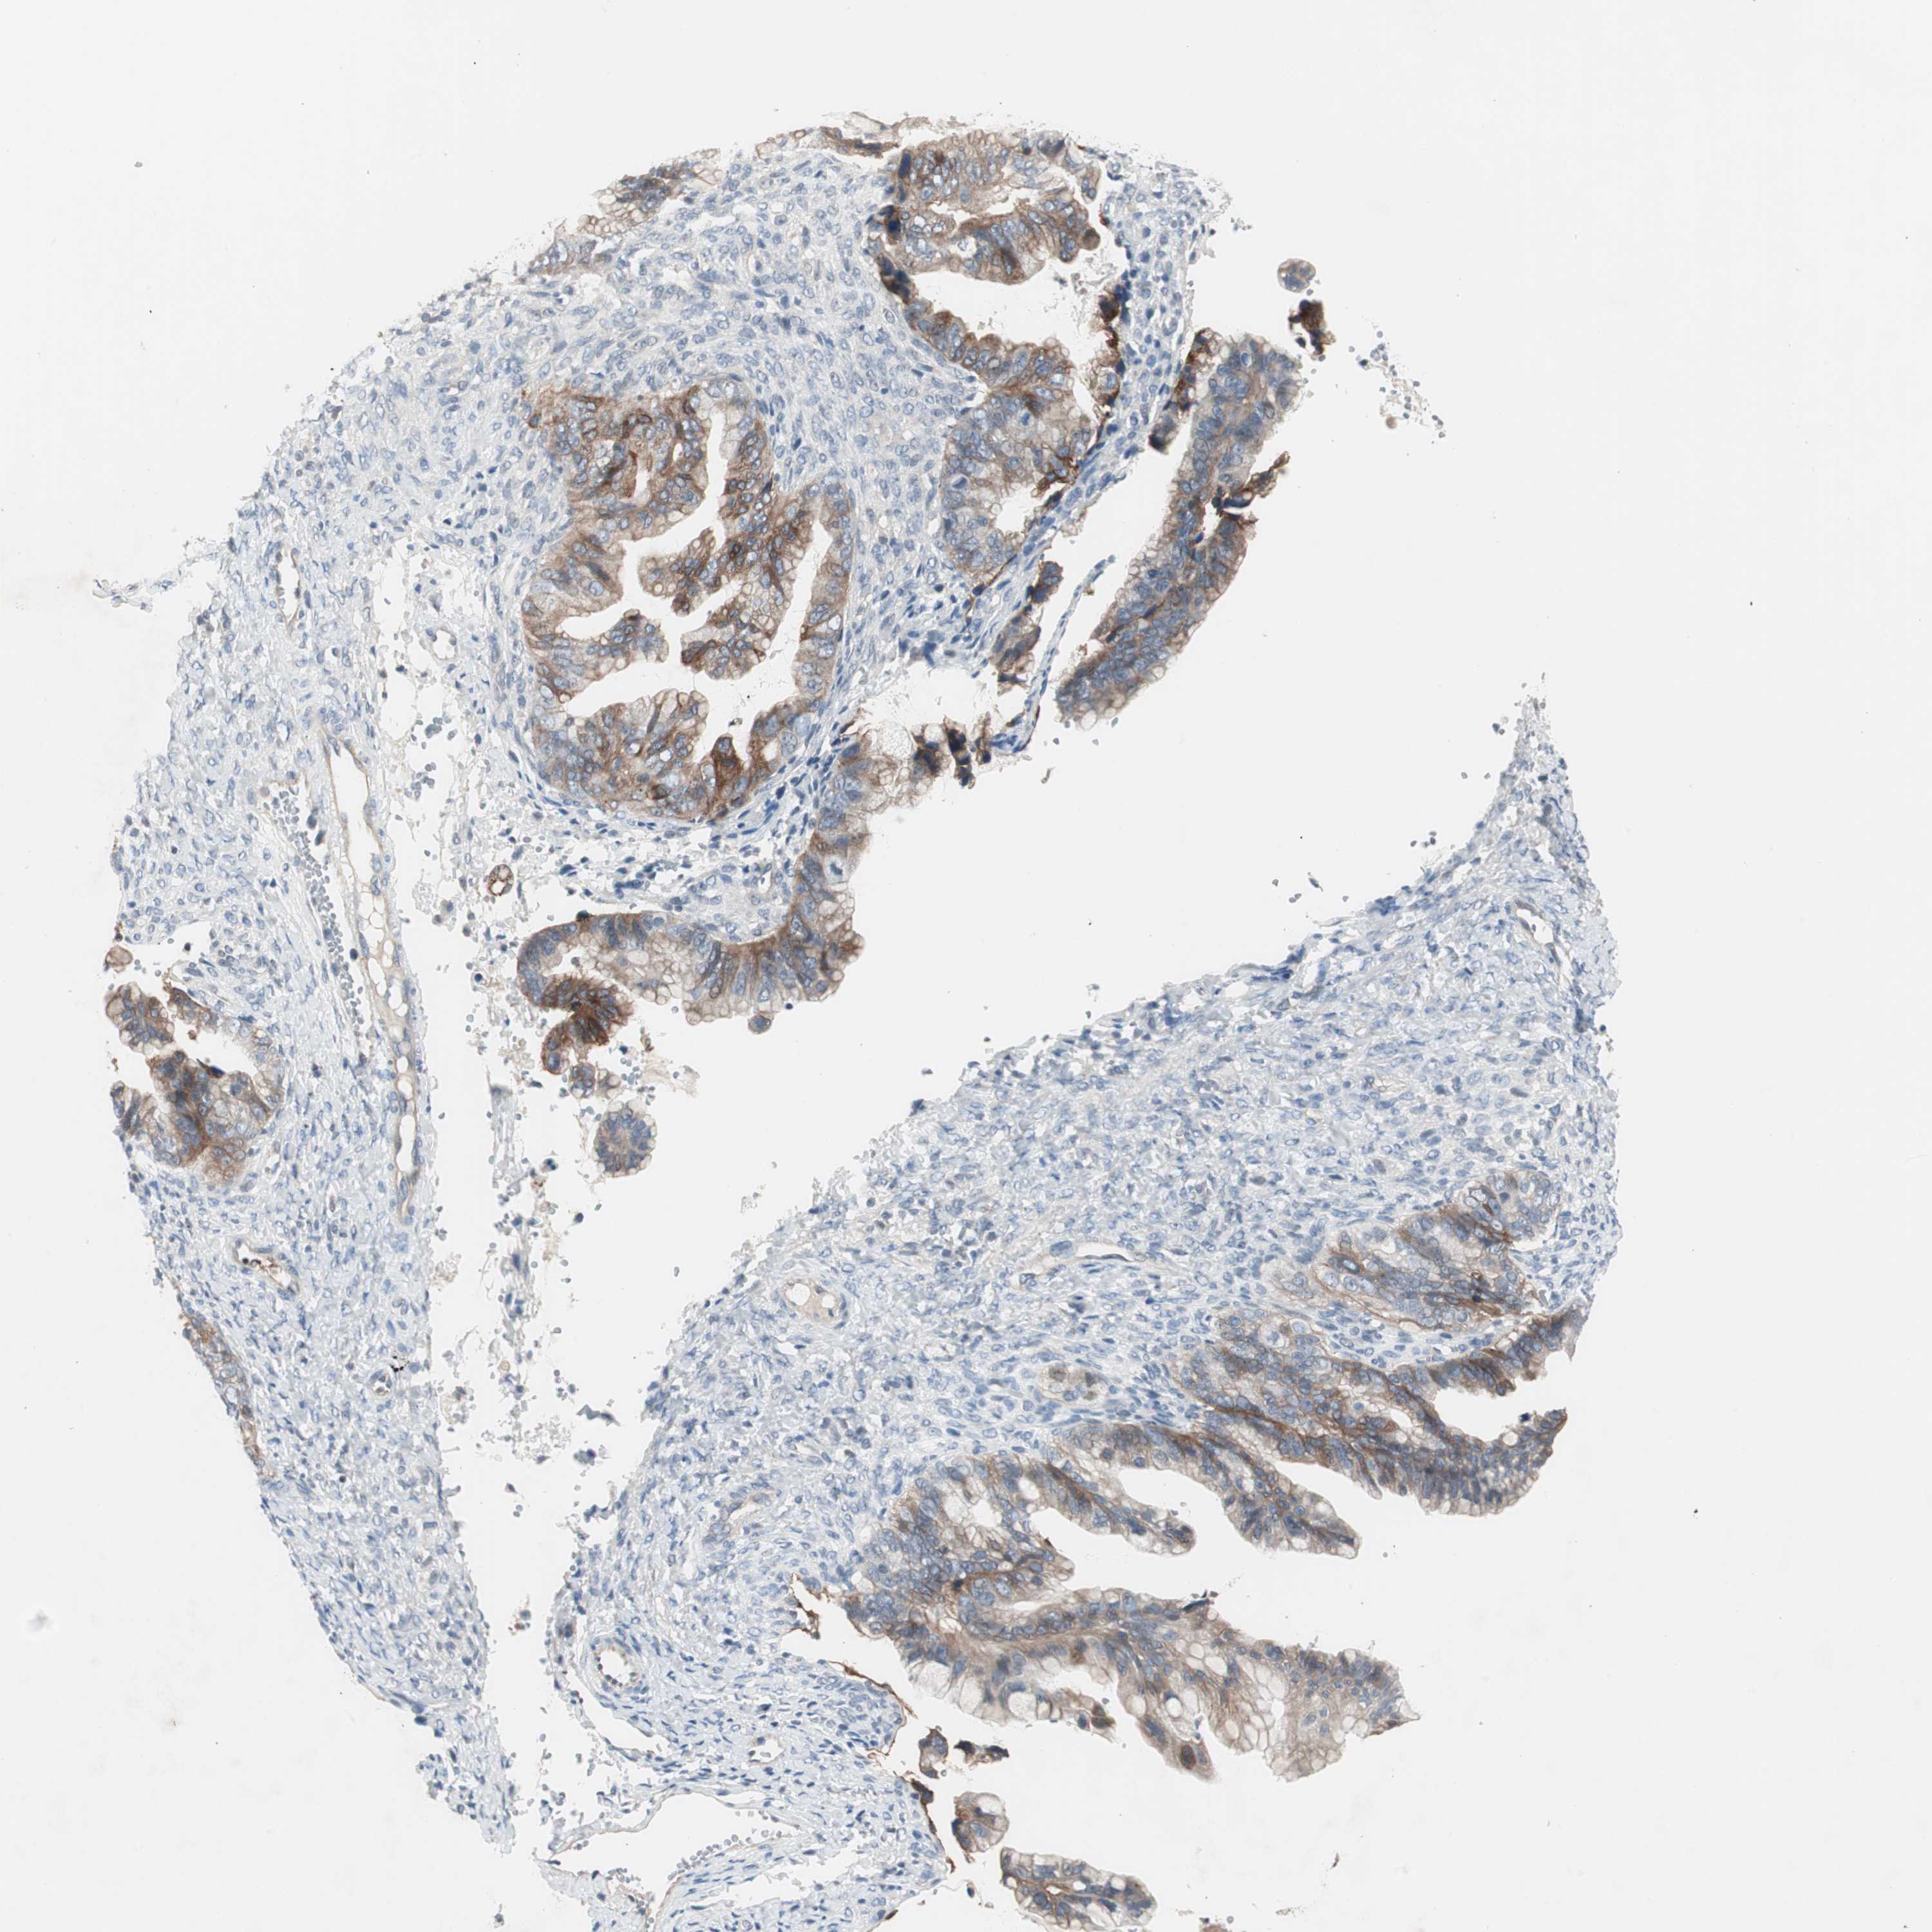

OVARIAN CANCER - Protein expressioni

A mouse-over function shows sample information and annotation data. Click on an image to view it in a full screen mode. Samples can be filtered based on level of antibody staining by selecting one or several of the following categories: high, medium, low and not detected. The assay and annotation is described here.

Note that samples used for immunohistochemistry by the Human Protein Atlas do not correspond to samples in the TCGA dataset.

Antibody stainingi

Antibody staining in the annotated cell types in the current human tissue is reported as not detected, low, medium, or high, based on conventional immunohistochemistry profiling in selected tissues. This score is based on the combination of the staining intensity and fraction of stained cells.

Each image is clickable and will lead to virtual microscopy that enables deeper exploration of all samples and also displays staining intensity scores, fraction scores and subcellular localization as well as patient and tissue information for each sample.

Antibody HPA036348

Antibody HPA036349

Antibody CAB002422

Antibody CAB005258

Cystadenocarcinoma, serous, NOS

Carcinoma, NOS

Cystadenocarcinoma, mucinous, NOS

Carcinoma, endometroid